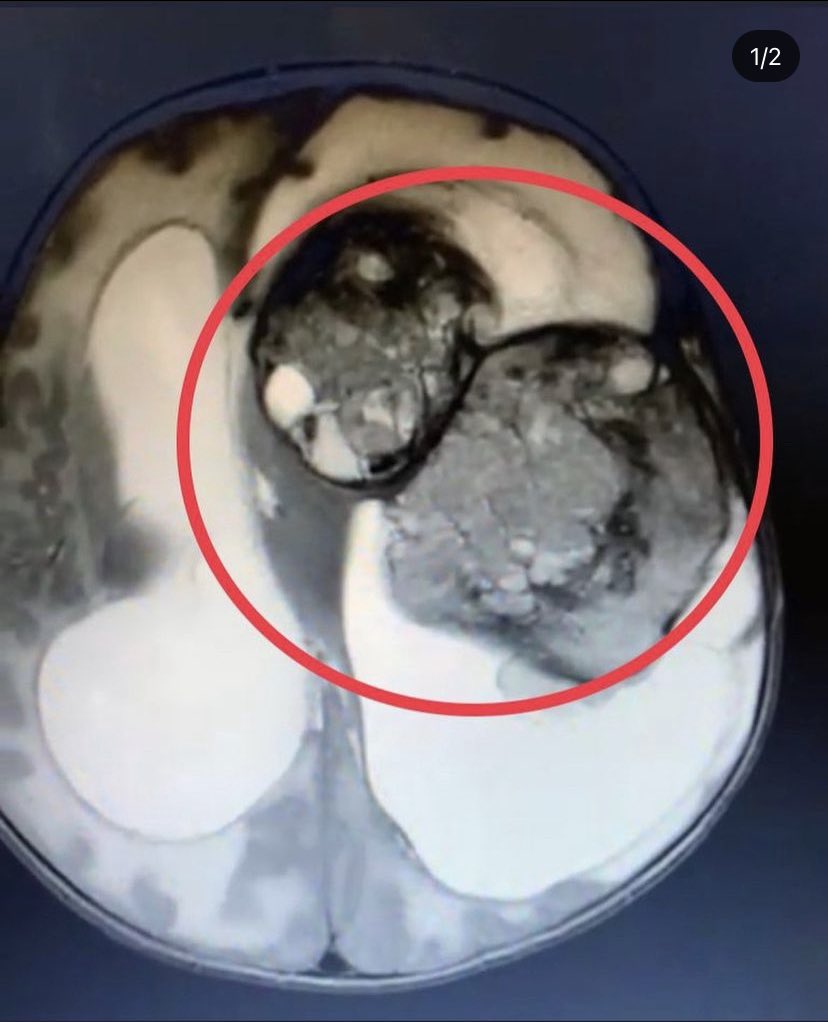

This month is #BrainTumourAwarenessMonth 16,000 people a year are diagnosed with a brain tumour and of those only 12% survive beyond 5 years. This isn’t good enough and more money must be invested in fighting this truly awful disease. #RouxsArmy